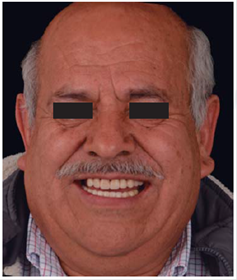

Este reporte documenta el tratamiento de un paciente masculino de 68 años de edad. Comenta tener dificultades masticatorias y digestivas debido a importante desgaste dental, se dice incómodo al sonreír; no refirió padecimientos sistémicos, fumó durante ocho años, diagnosticado con hipertensión arterial controlada. Se observa atrición generalizada, ausencia de dientes 14, 15, 16, 46 y periodonto sano (Figuras 1a4). Los dientes 13 y 37 presentaban tratamiento de conductos y periápice sano, sin restauración (Figura 5).

Para cuantificar la reducción de DVO, se examinó el perfil facial y la estética mediante análisis fotográfico y vídeo (Figuras 6y7). Además de realizar un cuidadoso análisis del montaje de los modelos diagnósticos en articulador semiajustable (Figura 8). También se examinó el esquema oclusal (presentaba relación borde a borde) y la estructura dental con la que se contaba (Figura 3). La revisión dinámica fue clave para determinar que el paciente exhibe una línea de sonrisa alta (Figura 9).

Se controló al paciente por espacio de un mes y medio para verificar su fase de adaptabilidad al tratamiento y su condición fue satisfactoriamente estable, cómoda y sobre todo funcional (Figuras 42a45).